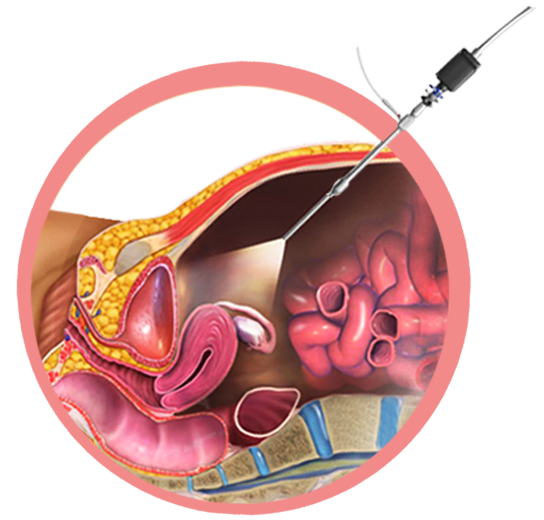

Our physicians are experts at minimally invasive surgical techniques. Minimally invasive surgical approaches emphasize small, limited incisions and surgical care as an outpatient. Our surgeons are skilled in advanced laparoscopic and hysteroscopic procedures.

Laparoscopic procedures can be performed using small incisions of around 0.5 to 1.5 cm that can be made far away from the surgical site.

Small, thin surgical instruments can then be passed through the incision and threaded through to the operational site.

The whole procedure is carried out using a laparoscope which is a small tube with a camera at the tip that can be used to relay images from inside the body to a TV monitor.

Our hospital provides a wide range of surgical services in order to either correct abnormalities of the female reproductive tract and promote fertility. Our expertise in the field proper diagnose as well as performing remedial surgeries along with our experience to handle such cases is the key to our success. Our in-house accurate diagnose help the patients to know exact problem; we recommend hysteroscopy + laparoscopy to better diagnose the problem.